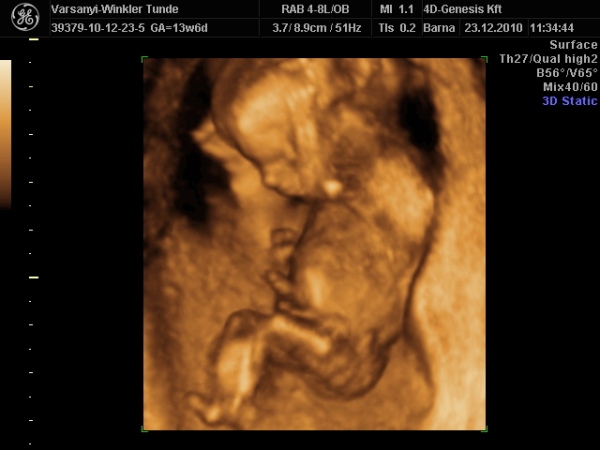

)2010.12.23 11:37